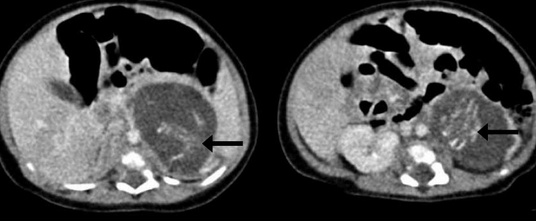

▼透过超音波检查,医生发现在女婴的脊椎和内脏间,有着诡异的两团组织,但看起来绝不是肿瘤!经过详细鉴定后,才确定那是两个胚胎!也就是说,这位女婴身体内还有着一个8週大和10週大的宝宝。

隐藏在香港小女婴体内的两个胚胎虽然已发展出脐带、四肢、脊椎、肠道和脑组织,但最后医生也只能把他们移除。这样的医学案例实在令人难以置信,不过它还是在世界上不断发生,太奇妙了!